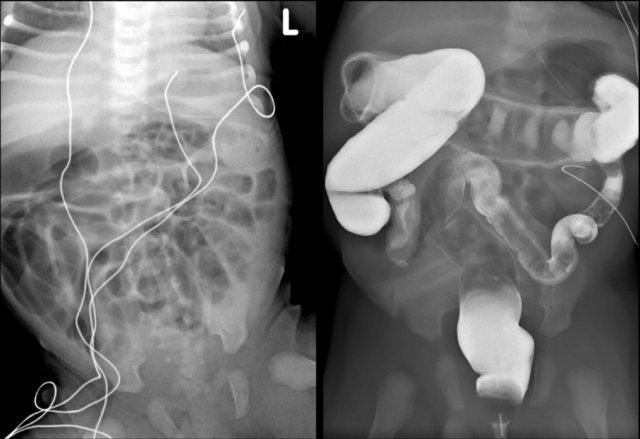

Đây là một trẻ sơ sinh bị xoay ruột bất thường.

Phim X-quang bụng không đặc hiệu (hình bên trái)

Chụp X-quang đường tiêu hóa trên cho thấy rõ ràng ruột non nằm bên phải cột sống.

Xoay ruột bất thường chỉ trở nên có triệu chứng khi xoắn ruột xảy ra do mạc treo ngắn hoặc khi dải Ladd gây tắc nghẽn tá tràng.

Cả hai biểu hiện này đều